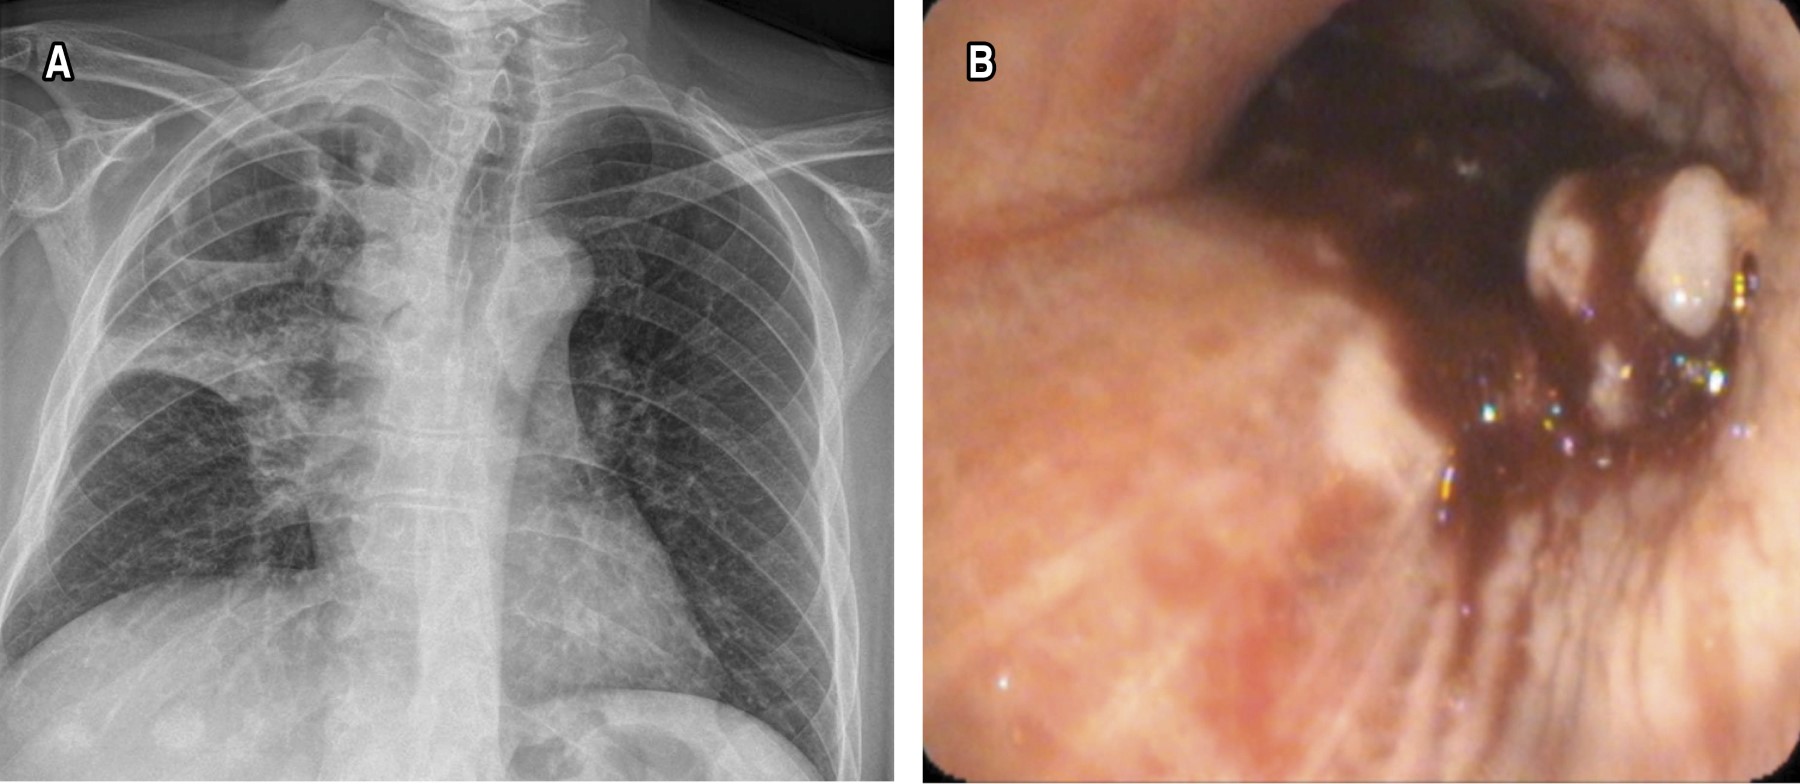

Tumor endobronquial se identificaron 64, la localización más frecuente fue en el árbol bronquial derecho, con 39 (60.9%) pacientes. De éstos, 19 (29.6%) se encontraron entre los segmentos 6 a 10 derecho, 12 (18.7%) en el lóbulo medio y ocho (12.5%) en los segmentos 1 a 3. En el árbol bronquial izquierdo, se observaron 25 casos (39%). De éstos, seis (9.3%) se encontraron entre los segmentos 6 a 10 izquierdo, 10 (15.6%) en la língula y nueve (14%) en los segmentos 1 a 3 (Figuras 1 y 2).

Lesiones infiltrantes de la mucosa con aumento de vascularización se observaron en 21 pacientes.

De las 63 muestras de tumores endobronquiales, 24 (38.1%) correspondieron a carcinoma de células escamosas, 19 (30.2%) a adenocarcinoma, ocho (12.7%) a cáncer pulmonar de células pequeñas, cinco (7.9%) a carcinoma ductal infiltrante, cuatro (6.3%) a tumor germinal y tres (4.8%) a carcinoma renal de células claras.

En cuanto a las lesiones infiltrantes de la mucosa con aumento de vascularización, de los 17 pacientes, 13 (76.5%) corresponden a adenocarcinoma y seis (35.3%) a carcinoma de células escamosas. Dos pacientes con compresión extrínseca presentaron adenocarcinoma pulmonar.